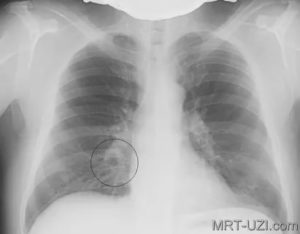

На рентгеновском снимке грудной клетке специалист может обнаружить усиление рисунка легких очагового или диффузного характера в верхней или нижней зоне органа. Иногда это исследование может показать и наличие кистозных просветлений небольшого размера. КТ дает возможность выявить различные виды затемненностей в легких и больше сказать о процессе образования фиброзных изменений.

Для диагностики фиброза также используют рентгенологические методы:

- рентгенограмма необходима для визуализации легочного рисунка,

- компьютерная томография дает возможность увидеть очаговые, периферийные, субплевральные, сетевидные затемнения органа,